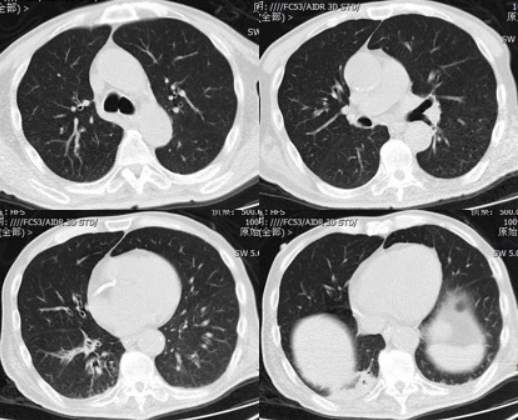

气道阻力升高、呼吸系统顺应性降低、气体交换障碍均会增加呼吸功耗导致脱机失败[3]。本文所述患者慢阻肺急性加重、感染性休克病情控制后无法顺利脱机,气切后气管镜所见患者右肺中、下叶大量黄痰,肺泡灌洗液培养出多重耐药鲍曼不动杆菌及耐甲氧西林金黄色葡萄球菌,考虑存在院内感染。但患者入我科后血流动力学稳定,胸X线片及治疗后胸部CT(图5仅提示右下肺少许渗出影,血炎性指标大致正常,经积极抗感染及气管镜吸痰后感染控制可,体温正常,痰量明显减少。且患者临床未应用镇静药物,无严重代谢性碱中毒,无明确呼吸驱动不足的表现;肺顺应性和气道阻力大致正常,既往(2016-03-07)肺功能检查示:肺活量1.21 L(21.8%Pred),用力肺活量(FVC)1.21 L(28.8%Pred),第1秒用力呼气容积(FEV1)1.15 L(35.1%Pred)FEV1/FVC 95.5%,25%肺活量时最大呼气流量(MEF25)3.29 L/s(44.9%Pred)50%肺活量时最大呼气流量(MEF50)2.69 L/s(61.2%Pred)75%肺活量时最大呼气流量(MEF75)0.88 L/s(53.8%Pred),提示限制性通气功能障碍。气道或肺部病变并非其延迟撤机的主要原因。

为什么会出现呼吸机依赖以呼吸困难首诊的肌萎缩侧索硬化症及呼吸机依赖原因分析_https://www.jmylbn.com_新闻资讯_第12张

5  胸部CT(2018-08-09)